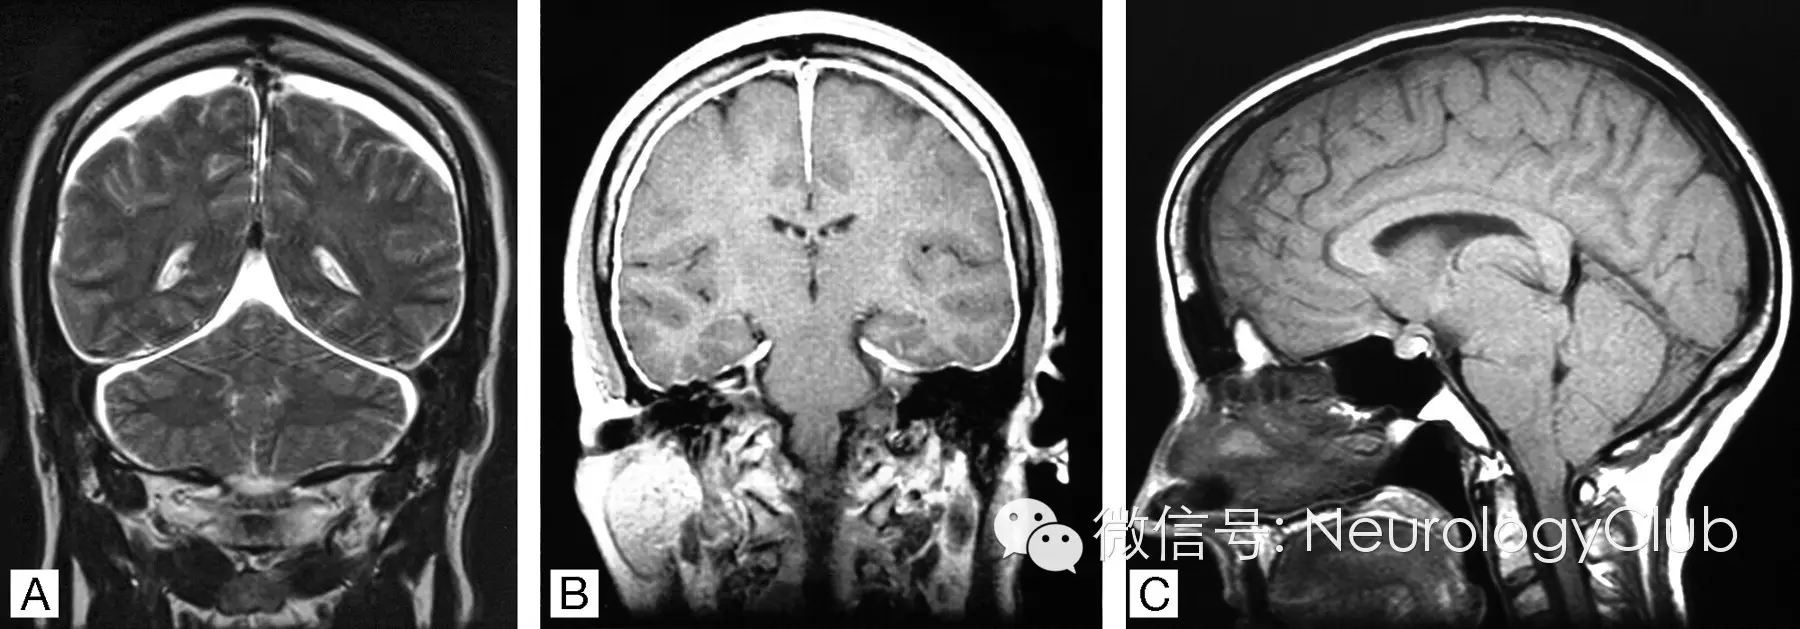

(a)弥漫硬脑膜强化;(b)小脑扁桃体疝;

(c)硬膜下积液; (d)弥漫脑水肿

(引自:Intracranial hypotension syndrome: A post dural puncture headache? Rev Colomb Anestesiol. 2013;41:57-60.)